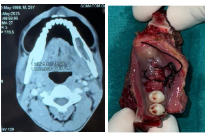

Cervico Facial Actinomycotic Osteomyelitis : A Single Center Experience

Global Journal of Pathology & Laboratory Medicine Volume 2, Issue 1, July, 36-46 Received: April 5, 2023, Reviewed: April 10,…